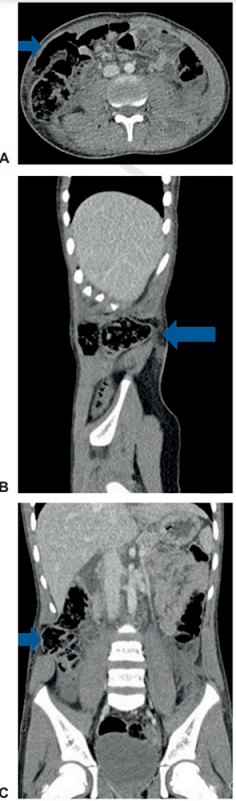

Masculino de 9 años, quien presentó trauma de alta energía como ocupante de la cabina trasera de un automóvil al sufrir una colisión frontal contra un autobús a alta velocidad. Fue evaluado y manejado inicialmente en hospital local, de donde remiten. Al ingreso se encontró estable hemodinámicamente, con signo del cinturón de seguridad, con dolor y defensa a la palpación abdominal, de predominio en el hemiabdomen derecho. Dado el mecanismo del trauma, se llevó urgente a TC de abdomen, donde se apreciaron hernias traumáticas de la pared abdominal anterolateral y posterior, asociadas a laceración hepática adyacente al ligamento falciforme y escaso líquido libre en cavidad (Figura 3), además de una fractura corporal de T12 no desplazada y fractura de elementos posteriores de L3 desplazada, con canal medular conservado.

Se programó para cirugía y se realizó herniorrafía videoasistida con cierre primario y sin material protésico, sin complicaciones. En cirugía se identificaron las hernias traumáticas de la pared, una anterolateral derecha con un defecto de 5 cm con ruptura del músculo recto, del oblicuo mayor, del menor y del trasverso hasta la región lateral, y otra hernia del retroperitoneo ipsilateral, que contenía asa de intestino delgado y salida de grasa perirrenal. En la evolución posquirúrgica presentó dolor importante, en especial relacionado con el trauma vertebral, necesitando de múltiples analgésicos, por lo que cursó posteriormente con íleo prolongado y debió permanecer hospitalizado por 9 días. Posteriormente, tuvo adecuada recuperación, con seguimiento ambulatorio a 36 meses sin recidivas.